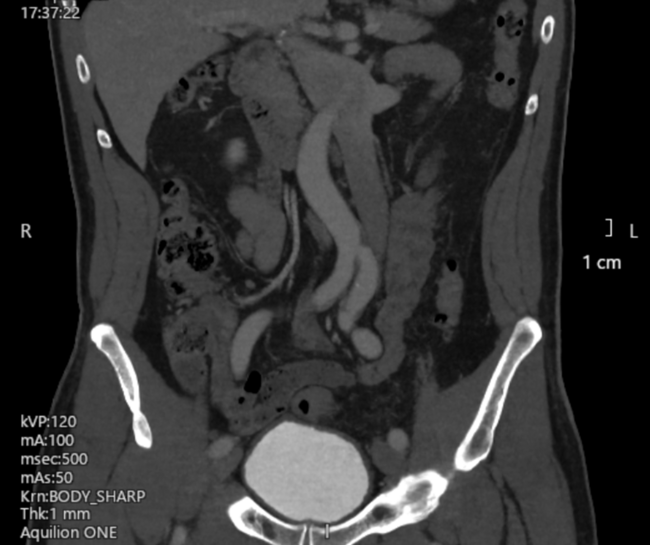

Video Supplement: Left-Sided Inferior Vena Cava: An Unusual Obstacle to Leadless Pacemaker Implantation

Video Supplement to "Left-Sided Inferior Vena Cava: An Unusual Obstacle to Leadless Pacemaker Implantation" (Clinical Image).